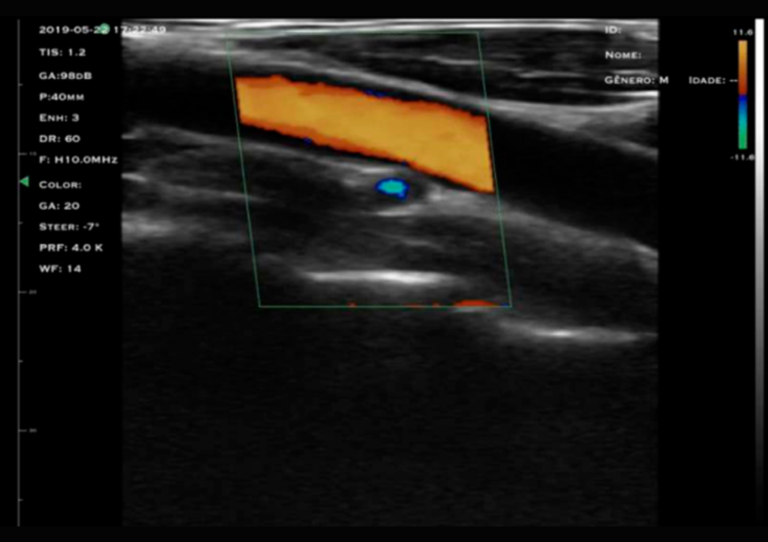

Com tecnologia linear e frequência de 3,5 a 5 MHz, o modelo M3D é a escolha ideal para quem busca alta resolução em exames profundos, com foco em versatilidade e precisão além do recurso do doppler.

O transdutor convexo oferece imagens confiáveis em profundidade, permitindo a visualização eficiente de estruturas abdominais e pélvicas, como fígado, rins, vesícula biliar, baço e órgãos reprodutivos.

Sua frequência mais baixa, associada à maior capacidade de penetração, garante versatilidade para diferentes tipos de exames, desde avaliações abdominais gerais até estudos obstétricos e ginecológicos, com boa definição mesmo em planos mais profundos.

Difere-se do modelo M3HD por conter os recursos de Color, PDI e PW e uma profundidade de até 280 mm.

Profundidade:

Linear (90 - 305 mm)

Modos:

B, B/M, Color, PDI, PW

Autonomia:

3 horas em uso contínuo, 6 horas em standby

Recursos:

Harmônica, Ganho Setorial, Suavizador de Ruído (192 elementos)

Ultrassom abdominal e point-of-care cardíaco, exames obstétricos e pré-natais, avaliações renais e identificação rápida de lesões e sangramentos internos.